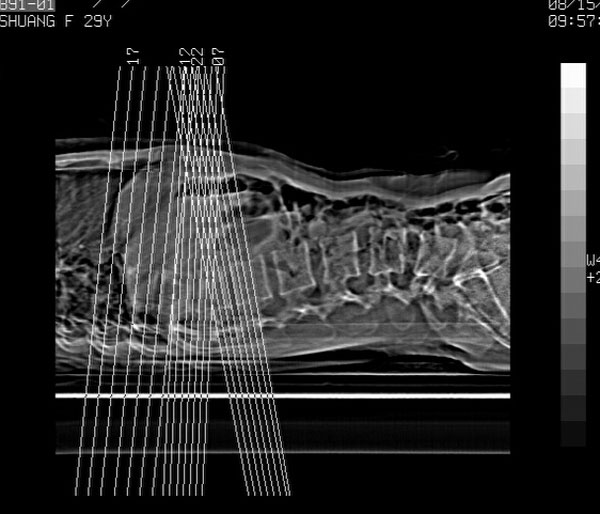

车祸致t12压缩性骨折,行ct扫描意外发现椎体多发肿瘤样病变,建议加拍骨盆平片,患者平常无症状。

1:胸腰椎多发破坏伴骨折,近似穿凿样,考虑骨髓瘤,但有好多不符只出1、发病年龄小、女性,2、病变似有硬化环。2:淋巴瘤可能性大,骨及脾脏均有改变(脾脏改变似与外伤关系不大)建议密切结合临床及相关检验进一步诊断,期待结果。

椎体多发性溶骨性破坏,部分融合,椎旁无软组织肿块、椎间隙正常,t12 压缩,脾脏增大,其内示多发低密度影,首先考虑多发性骨髓瘤。病人较年轻,平素无异常,转移瘤可能性小。